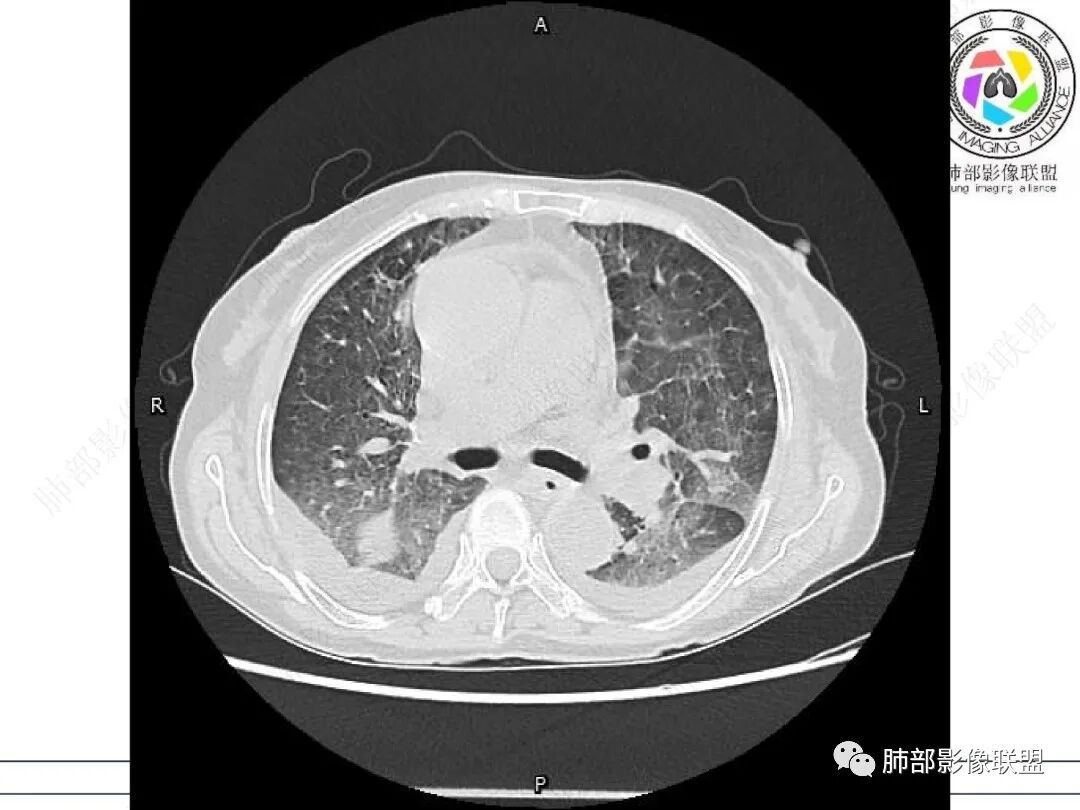

心脏大,胸腔积液,小叶间隔增厚,双肺磨玻璃影,考虑存在肺水肿,另双肺间质性炎性,类风关病史,考虑CTD-ILD,左肺上叶结核可能。

两肺叶后肋膈角区见多发蜂窝状结构破坏表现,双肺叶小叶间隔增厚,左肺上叶后段及舌段和右肺中叶胸膜炎性肉芽肿特点,双侧胸腔少量积液,有类风湿性关节炎治疗史,结缔组织相关性间质性肺病。

片状磨玻璃影,多发结节,类风湿肺炎?

发热,有类风湿性关节炎、糖尿病基础病,长期口服激素及免疫抑制剂,双肺多发磨玻璃影及小叶间隔增厚,蜂窝影,支气管扩张考虑非特异性间质性肺炎存在,左肺上叶不规则结节影,周围长毛刺局部肺气肿,考虑慢性炎症,结合pct及crp升高考虑细菌感染,另真菌g升高考虑结合宿主因素,真菌感染需要积极排除。

老年,外阴溃疡加发热,感染指标明显有异常,血气分析,过度呼吸及低氧血症,宿主因素,糖尿病和激素,基础疾病RA。影像,双下肺体积有缩小,有蜂窝?双肺磨玻璃,多发结节,双侧胸水。树芽不明确。是否有旧片,这个患者有UIP背景,是否感染或者UIP急性加重,或者基础上合并肺栓塞及肺水肿?长期激素,没有提供CD4细胞亚群,存在2种情况,1,风湿病没有压制住,肺考虑CTD相关性间质改变,压制过猛,结合感染指标,奴卡是有可能的。激素加糖尿病,结核也带排,激素加磨玻璃加G实验阳性,PCP也带排,临床信息太少,进一步排查

老年女性,有高血压糖尿病及类风湿性关节炎病史,发病前发烧。影像学两肺弥漫性磨玻璃影及斑片影,有渗出性病变亦有间质性改变,支气管血管束增粗,有牵拉扭曲有小气管扩张及间质增厚,两肺下叶胸膜下少许蜂蜜状影。两侧胸腔积液。考虑类风湿性关节炎肺内浸润?合并真菌感染?

老年女性,类风湿关节炎病史多年。发热。以两肺下叶为主弥漫磨玻璃及网格状透亮影,透亮度减低,局部小蜂窝状改变;两肺胸膜下散在几枚实性病灶;双侧胸腔积液。考虑RA-ILDNSIP

双下肺后肋膈角区见多发蜂窝,小叶间隔增厚,磨玻璃改变,,双侧胸腔少量积液,Crp明显升高,有类风湿性关节炎,糖尿病。甲氨蝶呤,托法替布治疗。会阴溃疡。考虑:1.免疫妥协2.pcp?巨细胞病毒?3.甲氨蝶呤致肺损伤?4.Ctd-ild.

类风湿病史,双肺小叶间隔增厚,散在磨玻璃密度增高影,双侧胸腔积液,患者免疫妥协,发热,PJP、病毒感染,类风湿相关性肺部改变

女,71,外阴疼痛2周,发热1周。类风关、高血压、高血糖、卵巢囊肿、肠粘连、胆囊结石等病史及相关药物治疗史。胸部CT:两肺弥漫磨玻璃,血管束增粗,两下肺后肋膈角多发蜂窝,对称分布,双侧胸腔少量积液,纵隔窗心脏大血管影明显增宽。考虑混合性病变,CTD-ILD,并肺水肿?并PJP?。

①影像表现复杂:较弥漫间质性改变,对称磨玻璃密度为主,小叶间隔增厚,有一定重力分布趋势,未见明显纤维化,气囊及蜂窝位于肺边缘,未见典型“月弓征”。心脏影增大,双侧胸腔积液。

这即可见于间质性肺病,也可见于真菌感染(如PJP)、病毒感染,类风湿,以及肺水肿等等。

一般而言,如存在磨玻璃密度影浑浊,有重力分布趋势,肺表面蜂窝影,胸腔积液等等,并不常见于单纯PJP,除非其他因素叠加。